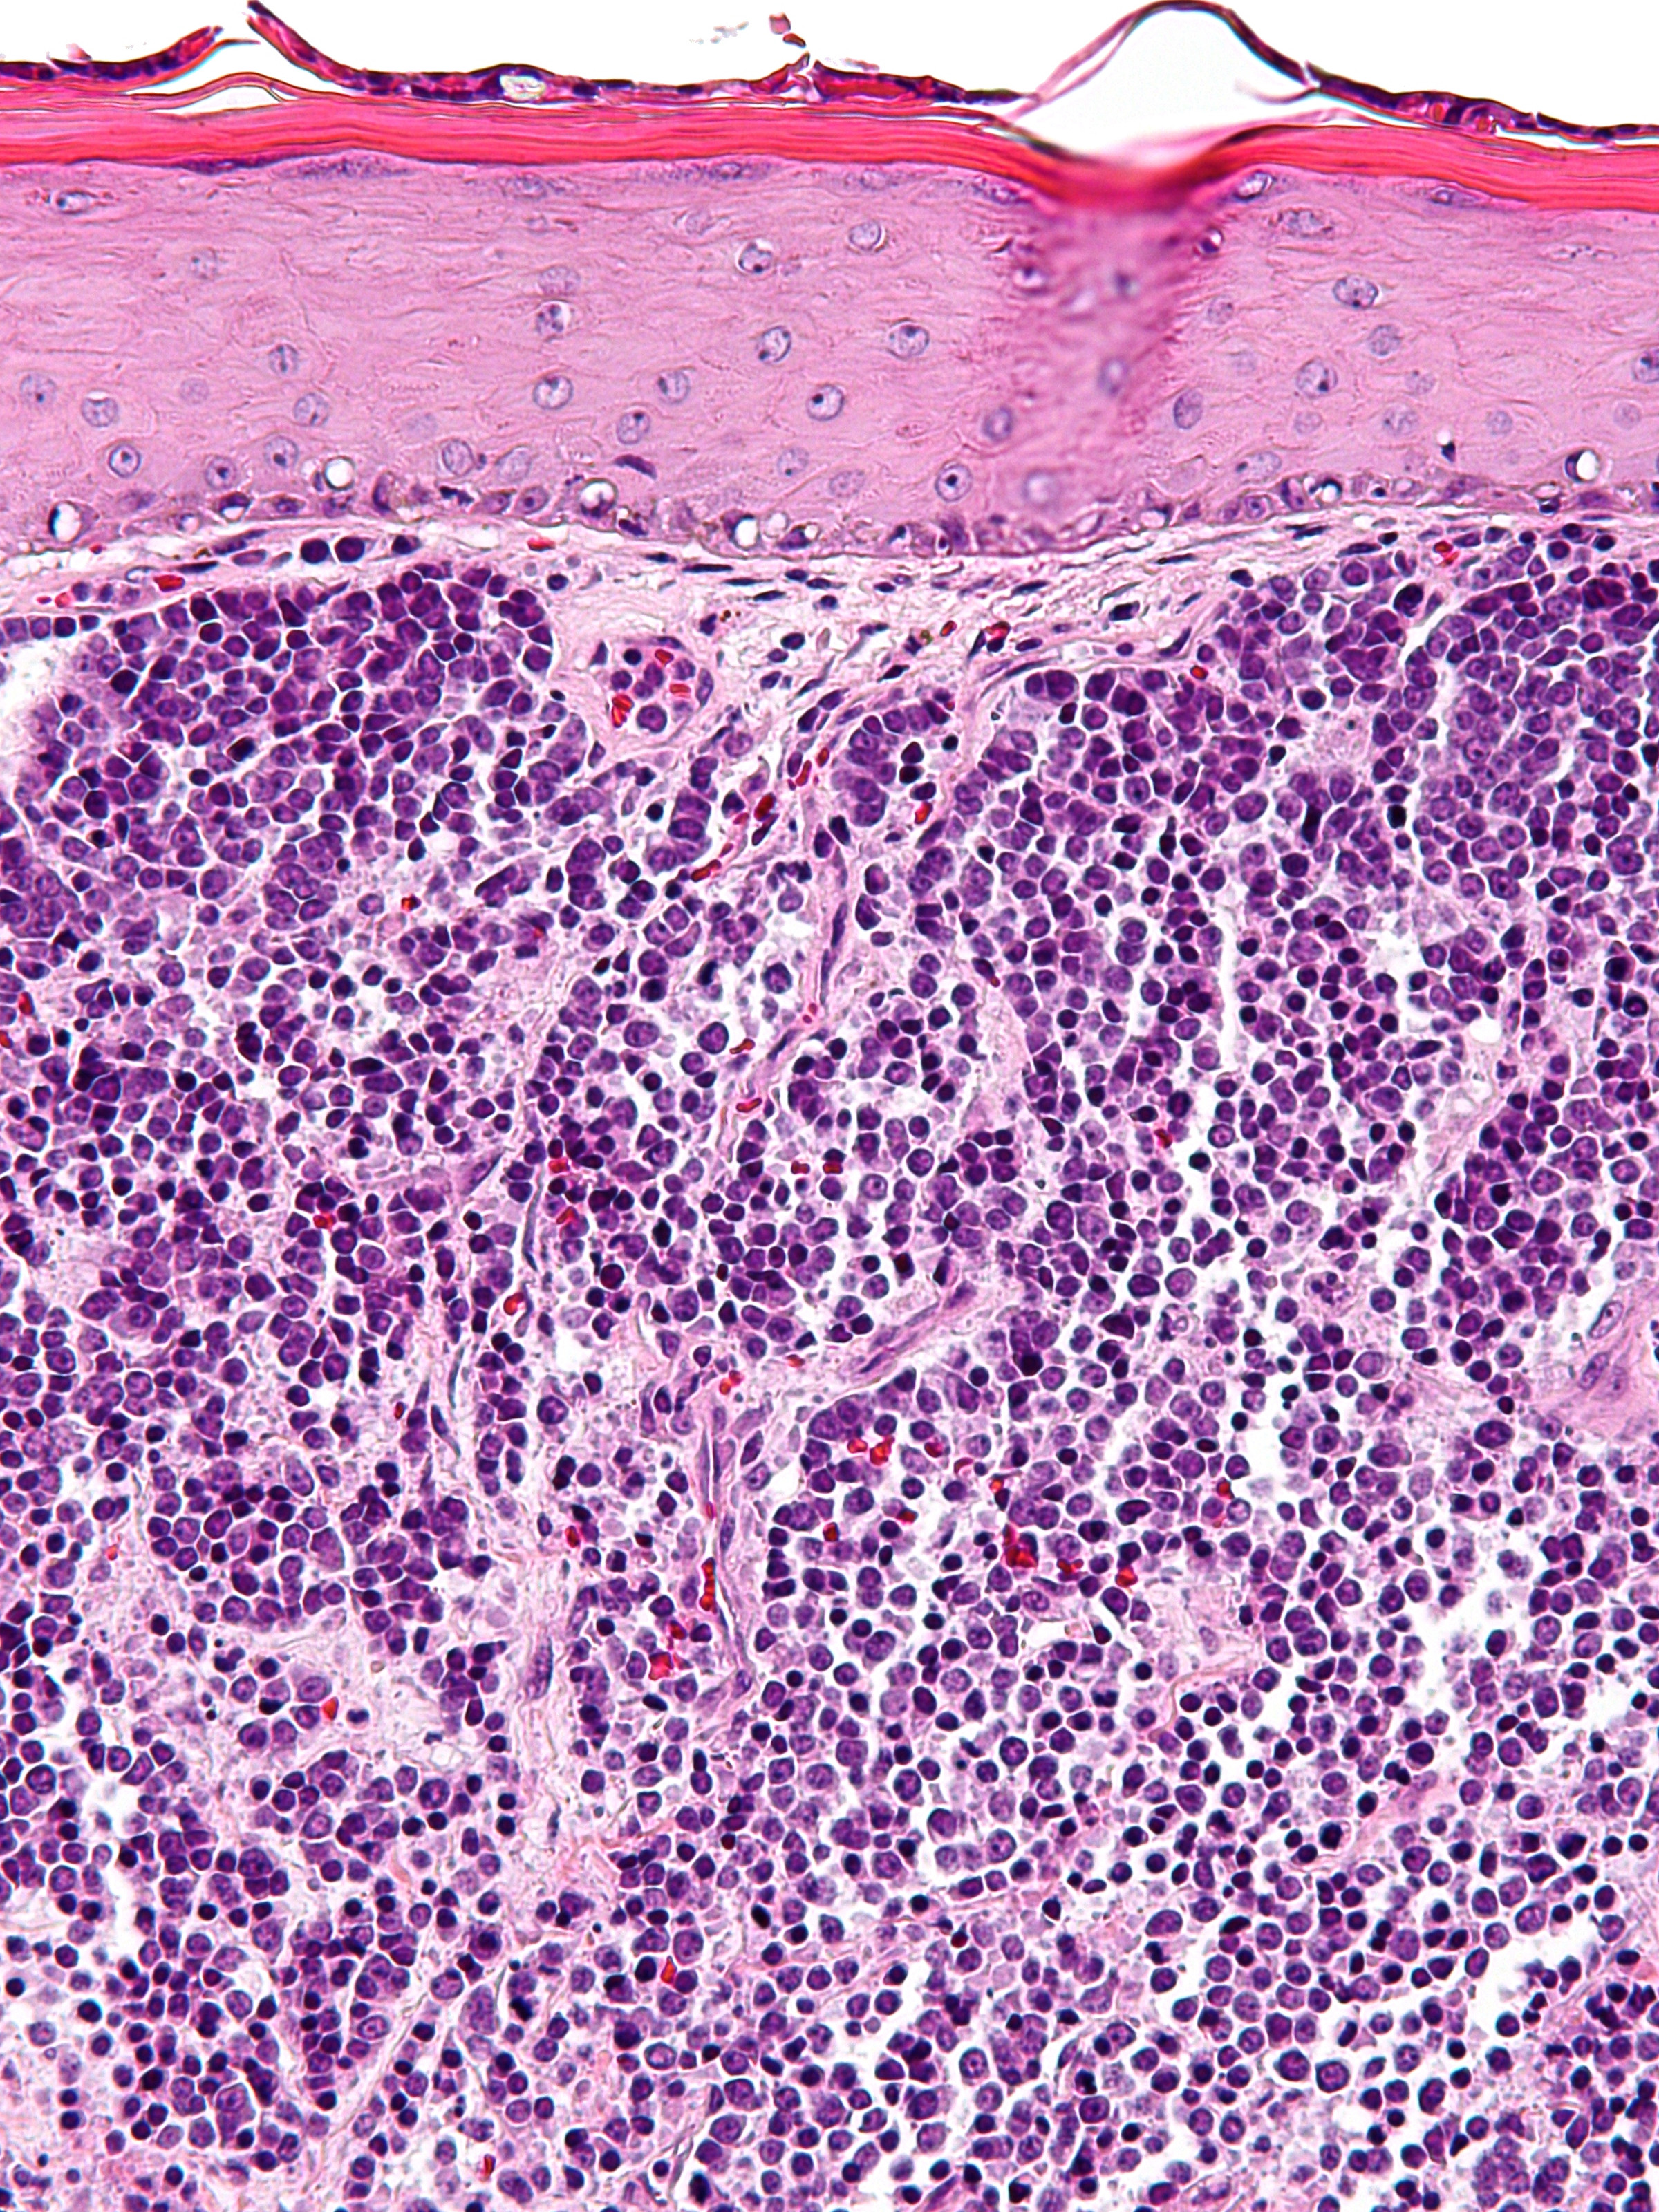

PA:

In de dermis, soms reikend tot in subcutis zijn velden van kleine ronde tumorcellen te zien (‘small blue round cells’). De tumorcellen zijn meestal gerangschikt in nesten, platen of strengen (trabekels). Soms worden ‘Homer-Wright pseudo-rosetten’ gezien, dat zijn kransen van tumorcellen rond een centrale zone gevuld met neurofibrillair materiaal, typerend voor neuro-endocriene tumoren. De tumorcellen zijn klein tot middelgroot en hebben zeer weinig cytoplasma en grote kernen t.o.v. de hoeveelheid cytoplasma. De celkernen vertonen een karakteristiek ‘salt and pepper’ chromatinepatroon (fijnkorrelig chromatine) met onopvallende nucleoli. Er zijn vele mitosen te zien. De tumor kleurt aan met cytokeratine 20 (CK20) en met neuro-endocriene markers (chromogranine A, synaptofysine, CD56). TTF (positief bij longcarcinoom) en S100 (positief bij melanoom) zijn negatief. Bij ongeveer 80% van de gevallen kan het Merkelcel-polyomavirus in de tumorcellen worden aangetoond.